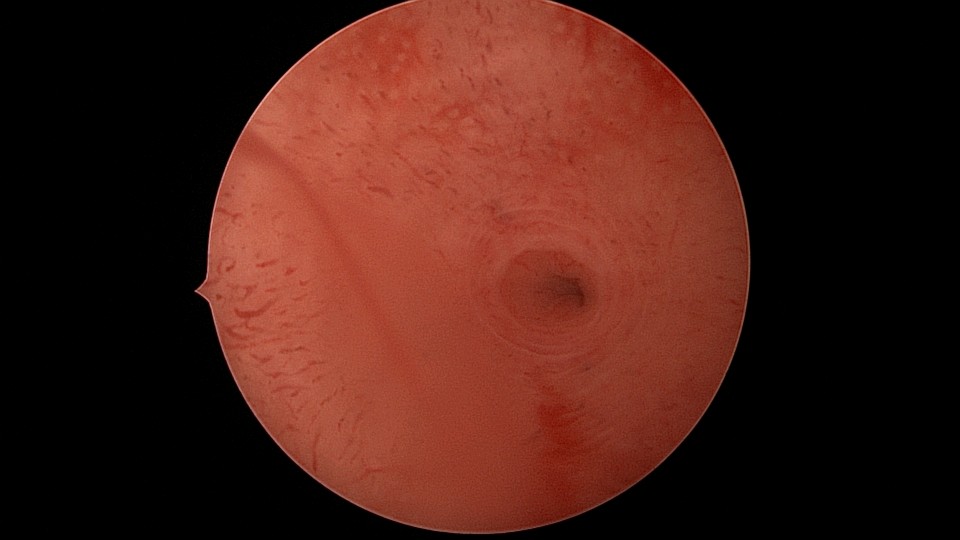

患者29岁,G1P0,继发不孕,2020年8月宫腹腔镜探查,大网膜与腹前壁多处粘连,子宫后壁与直肠前壁广泛粘连,宫腔中央型宽大柱状粘连,宫腔两侧少许粘连。电钩分离盆腔粘连,冷刀分离宫腔粘连,恢复宫腔形态,显露双侧输卵管开口,术中美兰通夜,双侧输卵管通畅。2020年10月宫腔镜二探取球囊,宫腔形态正常,双侧输卵管开口可见。2021年3月自然妊娠,外院足月分娩。现34岁,G2P1。